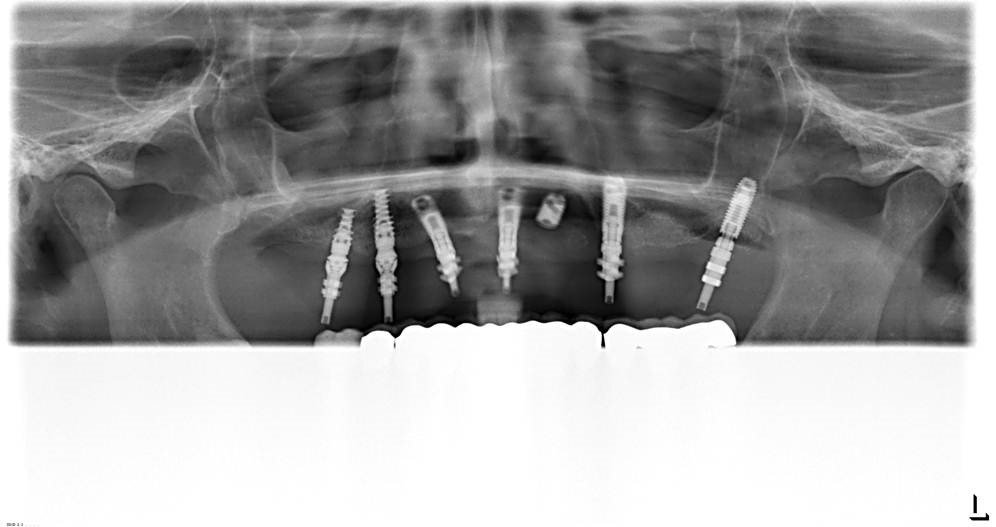

Buenas tardes, Adjunto la Radiografía panorámica y periapicales de los 3 Implantes superiores ( sector 2 ) . Necesitamos por favor, saber la marca para poder explantar el Implante 23 [...]

Buenos días: implantes conexión interna hexagonal np y rp, no sabemos la marca de estos implantes ( no son nobel,3i, straumann , galimplant). Arcada superior.